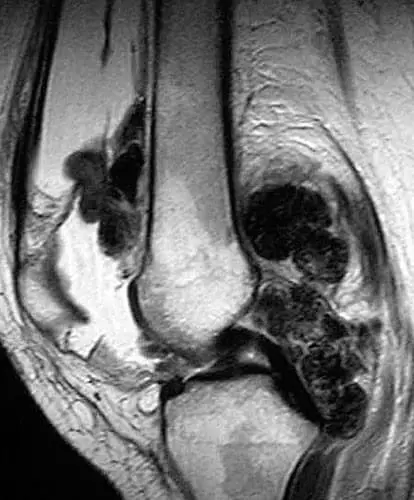

- Вільозно-нодулярний пігментний синовіт